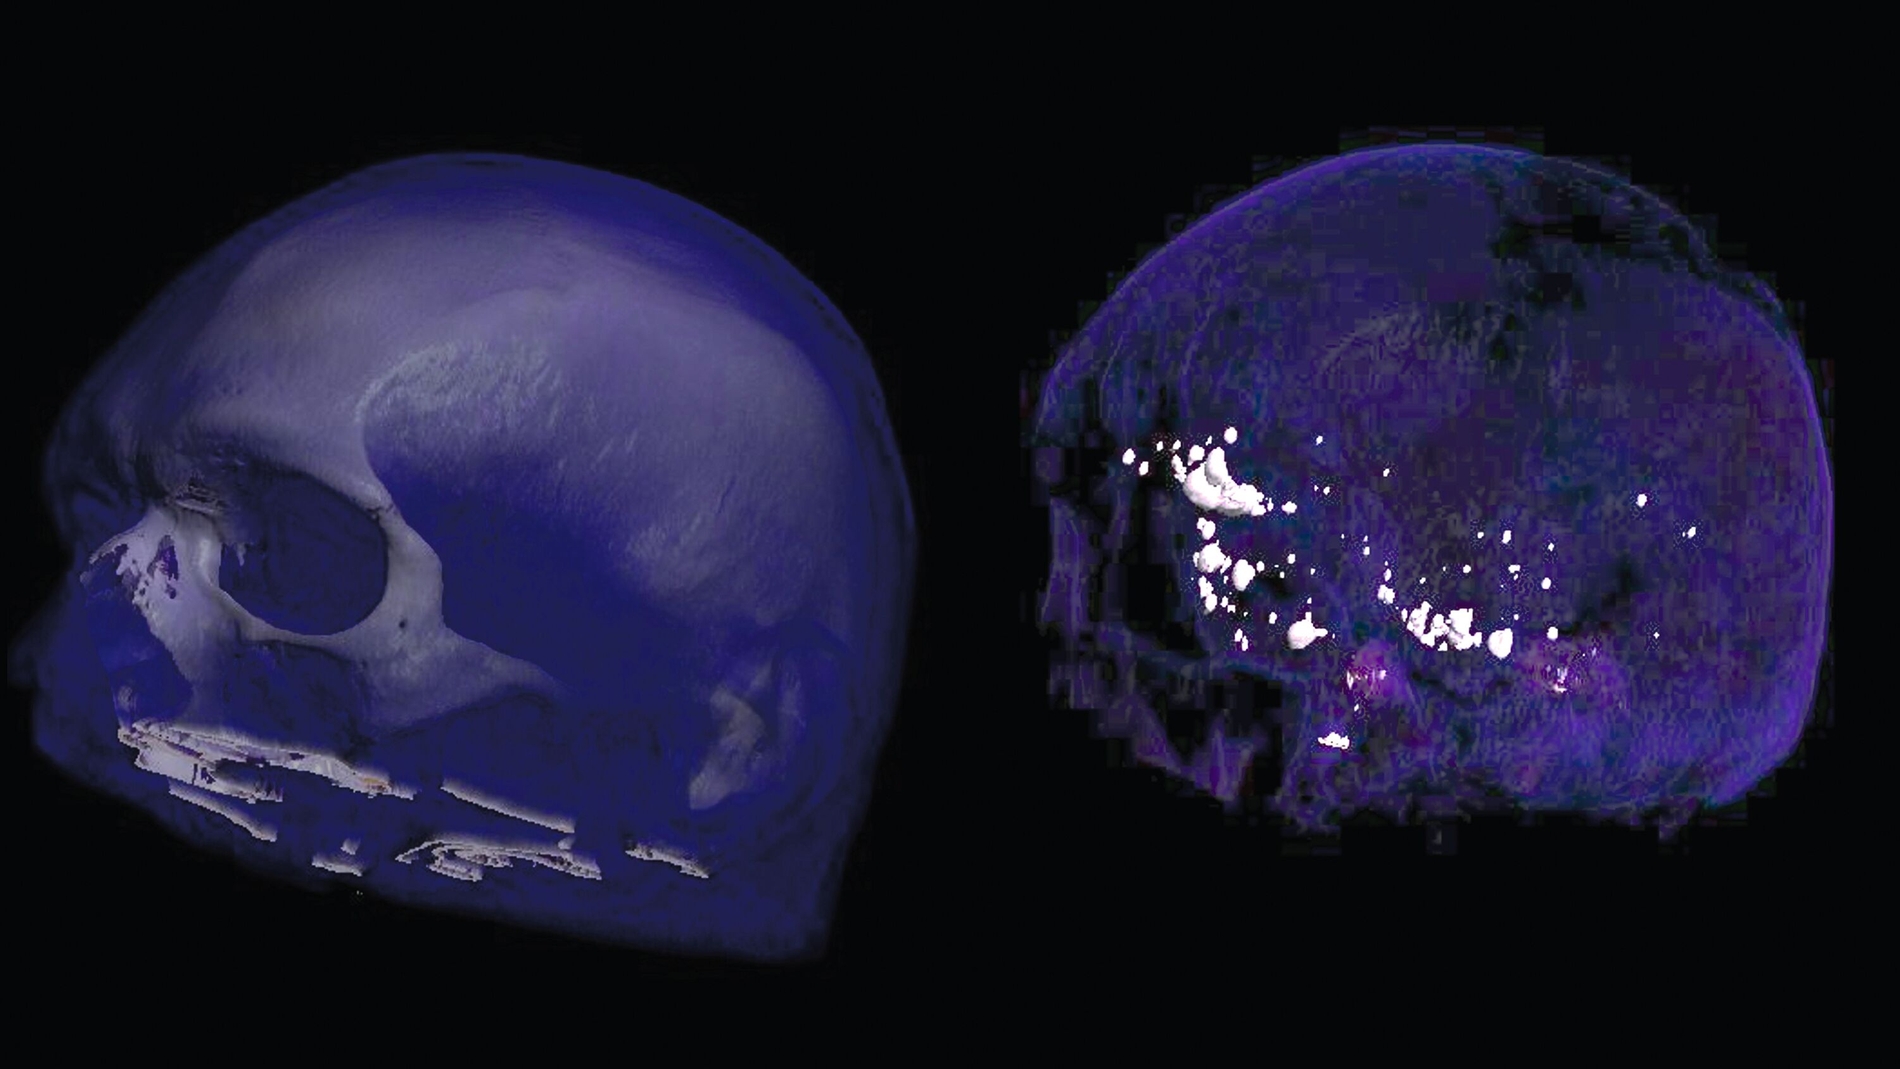

Das CT bestätigte multiple, teils rundliche, teils längliche, hoch röntgendichte Ablagerungen innerhalb der Liquorräume, vor allem supratentoriell und in den frontobasalen Abschnitten. Es zeigten sich keine Hinweise auf eine Liquorzirkulationsstörung, keine Raumforderungen, keine Mittellinienverlagerung und ein insgesamt unauffälliger Sella- und retrobulbärer Befund. Die basalen Zisternen waren frei. Die knöchernen Strukturen, einschließlich der Mastoidzellen, wiesen keine pathologischen Veränderungen auf.

Es ist bekannt, dass sich Lipiodol nach intrathekaler Applikation innerhalb der Liquorräume absetzen und dort dauerhaft verbleiben kann. Dokumentiert sind Fälle, in denen Lipiodol-Ablagerungen über Jahre hinweg sichtbar blieben, oft als kleine eingekapselte Globuli. Im Bereich der zahnärztlichen Bildgebung existiert nach unserem Kenntnisstand bislang lediglich ein einziger Fallbericht über die Darstellung von Lipiodolablagerungen – jedoch im Bereich der Speicheldrüsen nach Sialografie [Nocini et al., 2023].

Die röntgendichten Strukturen lassen sich mit sehr hoher Wahrscheinlichkeit auf die frühere Lipiodol-Gabe nach der Rückenmarksverletzung zurückführen. Der Patient wurde über die Natur des Befunds ausführlich aufgeklärt. Es besteht weder Behandlungsbedarf – noch eine echte Behandlungsmöglichkeit.